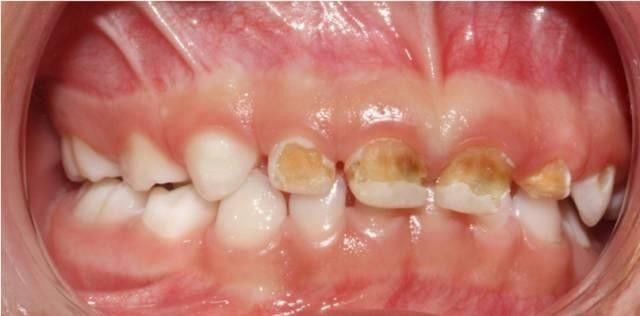

奶瓶龋最初在上颌乳切牙的唇面龈缘处出现白垩色斑点或带状脱矿,而后逐渐向下向旁边蔓延,侵蚀邻近的牙面形成环状龋,呈棕褐色,并最终发生牙冠折断,仅留下残根。

让孩子抱着奶瓶,就去上床睡觉,几周,几个月下来就会这样,妈咪再不重视也不去医院治疗。。。